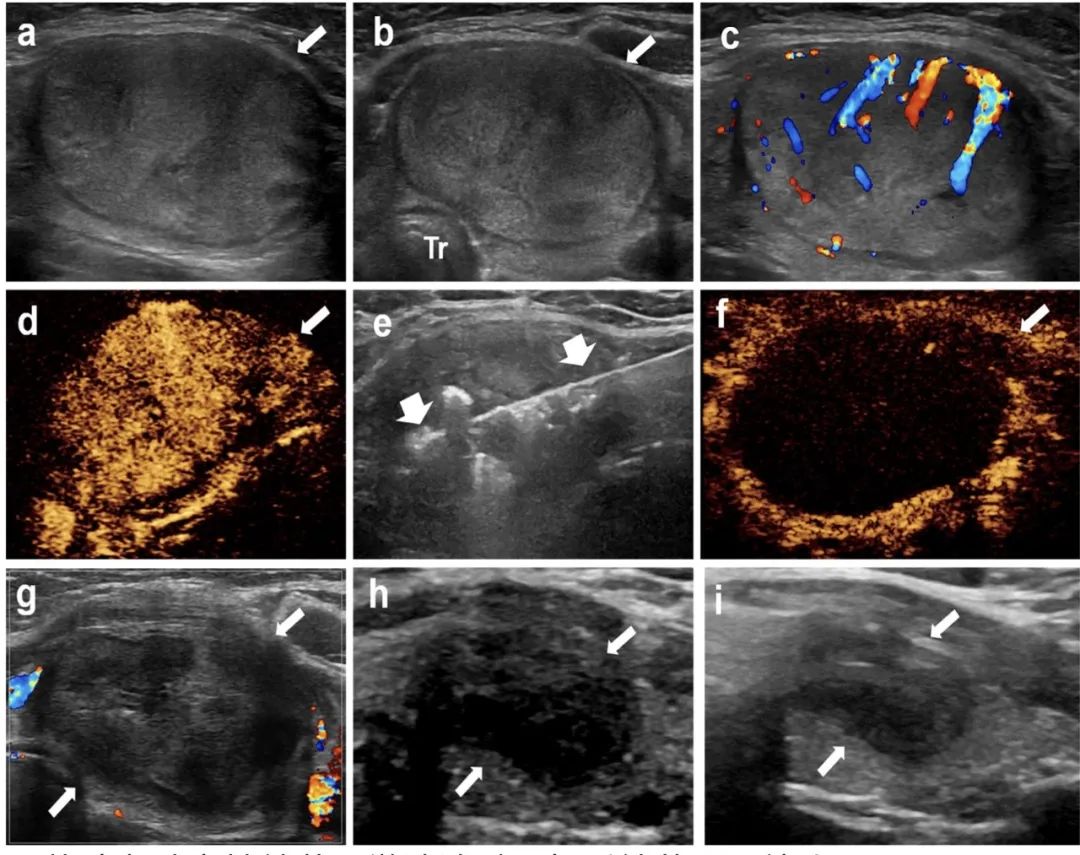

针对该问题,石文媛主任团队开创性地将微波消融技术应用于儿童良性甲状腺结节的治疗。连续分析了2018年1月至2021年12月在北京儿童医院接受经皮微波消融治疗的有症状良性甲状腺结节患儿25名,共 34枚结节。所有患儿均随访半年以上(中位随访时间12个月,范围6 - 48个月)。结果显示:经皮微波消融治疗后,结节体积逐渐减小(微波消融前中位体积5.86 mL,末次随访评估中位体积0.34 mL),末次随访评估体积缩小率达到85.03%,技术有效率达91.2%。结节相关压迫症状、美容相关问题均得到显著改善。术后一个月随访甲状腺功能维持在正常范围之内,提示微波消融在灭活甲状腺结节的同时不影响正常甲状腺功能。

甲状腺左叶实性结节,微波消融4年后结节明显缩小